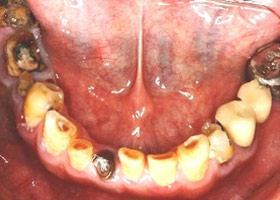

治療前

多顆缺牙及牙周病、蛀牙